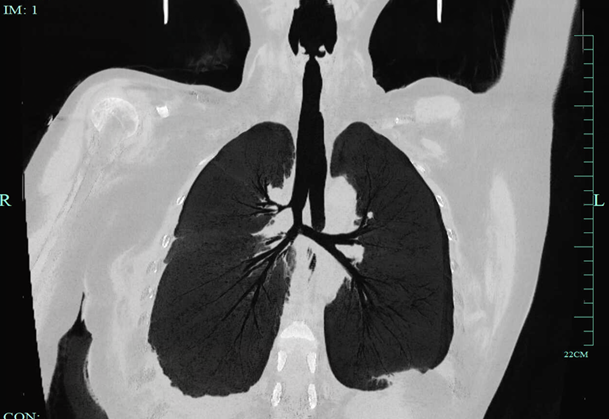

喘!胸部CT检查发现,一个肿瘤长在了她的气管隆突(又名气管隆嵴,是位于气管分叉处的内面,向上凸起的纵嵴)及左主支气管壁位置气管镜进一步发现,她的左主支气管大部分被肿瘤堵住了,肿瘤还长到了气管支气管的三岔口“隆突”的位置,严重影响两侧肺的通气。

这就是媛媛咳嗽咳痰、气喘吁吁、呼吸不畅的真正原因后面的活检病理结果为“非小细胞低分化癌”(恶性),如果不进行手术切除,任由肿瘤生长,她随时可能因窒息导致死亡02攻克气管重建难关,患者终于能正常呼吸韩威力主任向媛媛及家属介绍,人体的气管约9~11厘米,气管肿瘤是呼吸系统少见的病症,约占呼吸系统肿瘤的1%。

经过三个周期的新辅助化疗联合免疫治疗,她气管上的肿瘤较之前明显缩小,韩威力专家团队经过术前仔细评估后,决定为媛媛实行气管隆突重建手术一直以来,气管隆突手术是普胸外科难度最高的手术之一手术过程中气管隆突切断后,为保证患者正常供氧,需要在手术台上重新进行气管插管,配合不顺利会造成病人严重缺氧;病灶位置特殊,切除后气管与支气管剩余部分的口径大小不同,会造成吻合口不匹配;如果仅仅是将切断后的支气管与气管两端进行“套叠”,不仅有可能造成吻合部位的瘢痕狭窄、阻碍通气,而且会因拉扯增加对接口的张力,存在撕裂的隐患;新辅助化疗联合免疫治疗后的患者,更是病灶边界不清,分离困难;术中麻醉的配合也相当重要……。

术后第二天,媛媛就开始下床活动,术后提示两侧吻合口均通畅,保持呼吸气道的通畅和良好的肺功能,术后7天她就顺利出院了后续媛媛还要进一步接受放化疗治疗

术后气管重建03出现咳嗽、气急超过两周无缓解,建议做颈胸部CT